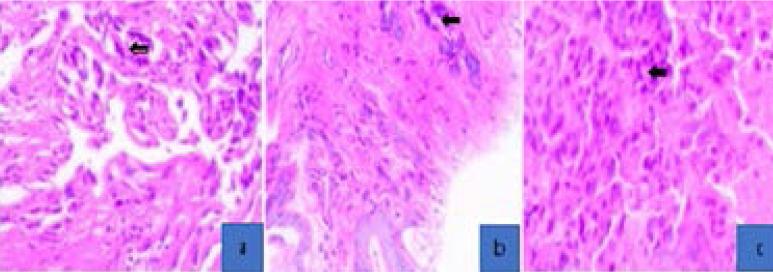

A total of 23 lung cancer tissues were retrieved. Histological types included eleven (47.8%) squamous cell carcinoma (SCC), six (26.1%) adenocarcinoma, two (8.7%) small cell carcinoma, two (8.7%) large cell carcinoma, 1 (4.3%) inflammatory myofibroblastic tumours and 1 (4.3%) pleural pulmonary blastoma. The results showed that the most affected age group was 60-69 years with most of the histological subtype in this age group being SCC. There was no statistically significant difference of histological subtypes across age groups, p=0.12.

共检索到 23 份肺癌组织。组织学类型包括 11 例(47.8%)鳞状细胞癌(SCC)、6 例(26.1%)腺癌、2 例(8.7%)小细胞癌、2 例(8.7%)大细胞癌、1 例(4.3%)炎症性肌纤维母细胞瘤和 1 例(4.3%)胸膜肺胚细胞瘤。结果表明,受影响最大的年龄组是 60-69 岁,该年龄组的大多数组织学亚型为 SCC。不同年龄组之间的组织学亚型无统计学显著差异,p=0.12。